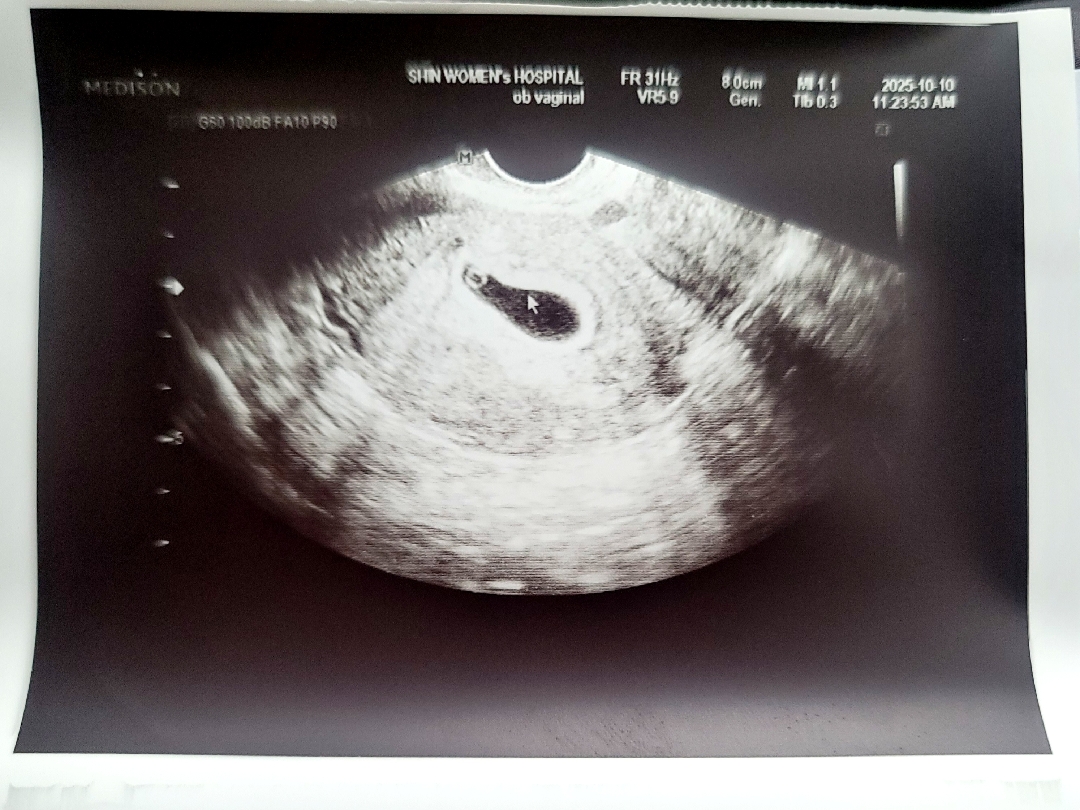

임신 5주3일차

드디어 난황 보고 왔어요 :) 엄청 또렷하고 선명한 집과 난황이 보여서 어찌나 안심되던지요ㅠㅠ 빈속입덧, 입덧, 복부뻐근함, 어지러움정도 번갈아가며 있지만 임신하기 두 달 전부터 엽산, 칼마디아, 활성오메가3 먹고 잠을 정말 푹잤는데 확실히 큰 도움이 된거같아요 :) 다들 잘 챙겨드셔요~ 내년 6월이 예정인데 비슷한 분들 계실까요~? 임신증상 공유부탁드려요!